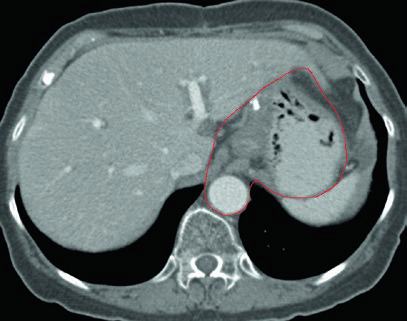

Caso 1: T1N1M0 Adenocarcinoma da Cárdia — Gastrectomia Total

Neste caso, o CTV engloba a anastomose esofagojejunal, o ligamento hepatogástrico, a artéria celíaca e o hilo esplênico. Como se trata de gastrectomia total em tumor da cárdia com linfonodo positivo, não há remanescente gástrico a incluir, mas os volumes nodais devem ser amplos.